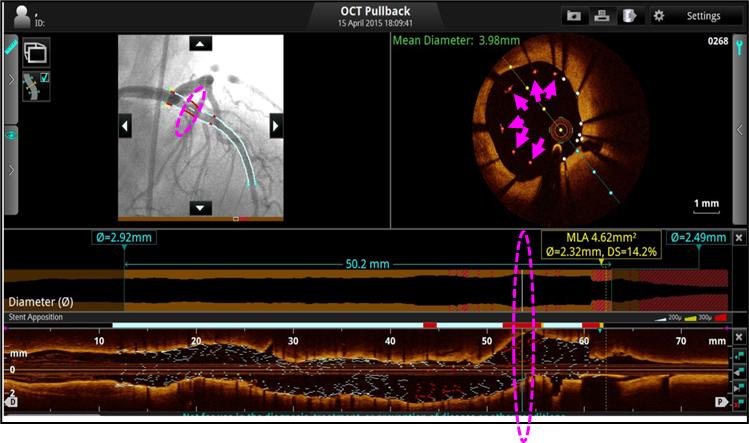

2、ACR造影融合——评估支架扩张情况

远端评估:支架远端边缘如果AS(面积狭窄率)≥20%,则需要进一步扩张处理。

近端评估:支架近端边缘如果AS(面积狭窄率)≥20%,则需要进一步扩张处理。